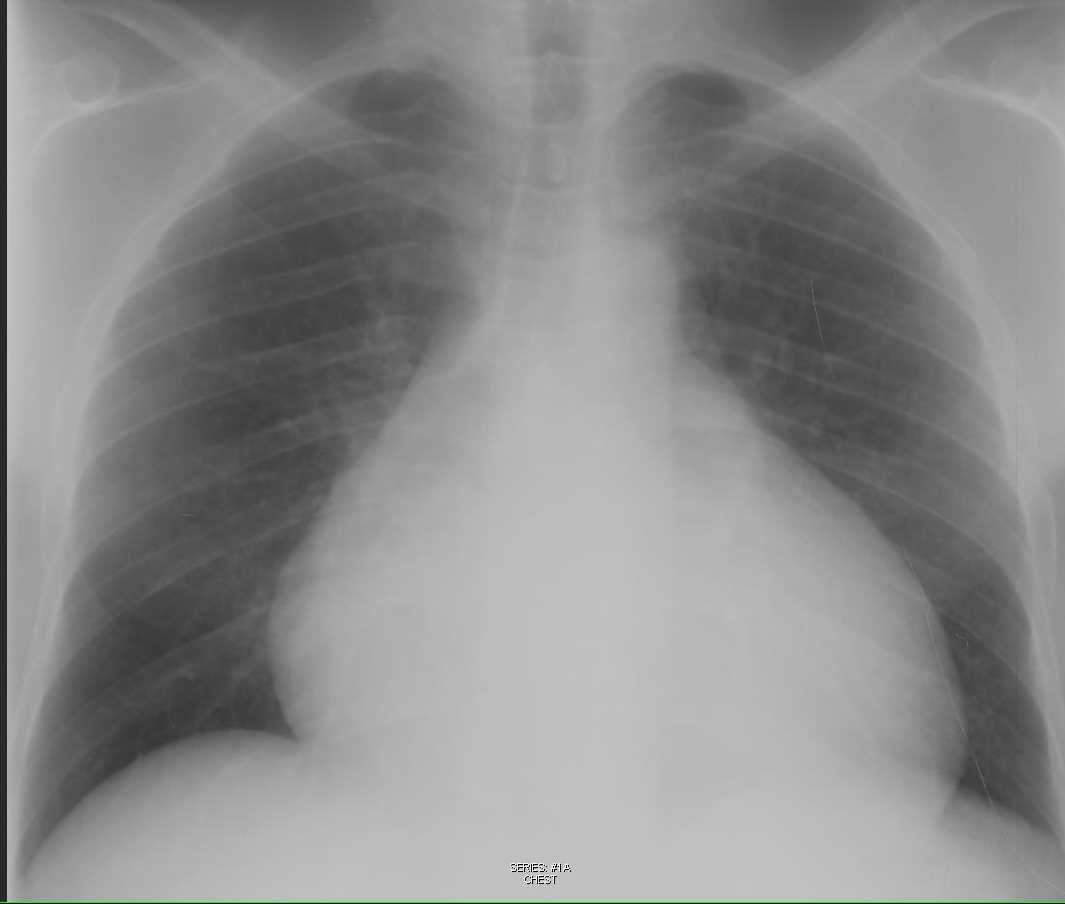

Chest Xray of case 3 showing pericardial effusion and left sided

Pericardial Effusion Lateral Chest X Ray . The oreo cookie sign refers to the appearance of pericardial effusion on lateral radiographs of the chest. Lateral cxr of pericardial effusion. Pericardial effusion may cause diffuse st elevation and low voltage on an ecg, though this is not always. A small amount of pericardial fluid may be visualized in asymptomatic normal subjects. Ct demonstrated most of the fluid to lie in the.

Lateral cxr of pericardial effusion. Pericardial effusion may cause diffuse st elevation and low voltage on an ecg, though this is not always. The oreo cookie sign refers to the appearance of pericardial effusion on lateral radiographs of the chest. Ct demonstrated most of the fluid to lie in the. A small amount of pericardial fluid may be visualized in asymptomatic normal subjects.